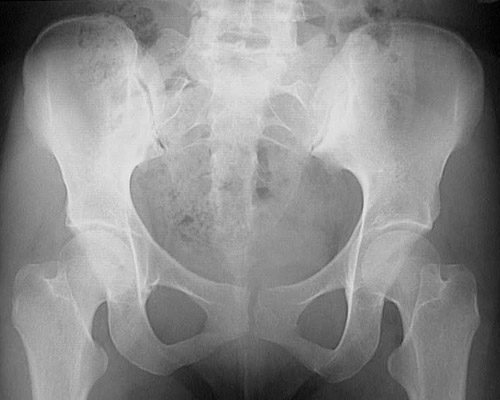

This radiograph of the pelvis demonstrates a sacroiliitis on the left, with narrowing and sclerosis of the sacroiliac joint. The SI joint on the right appears relatively normal by comparison.